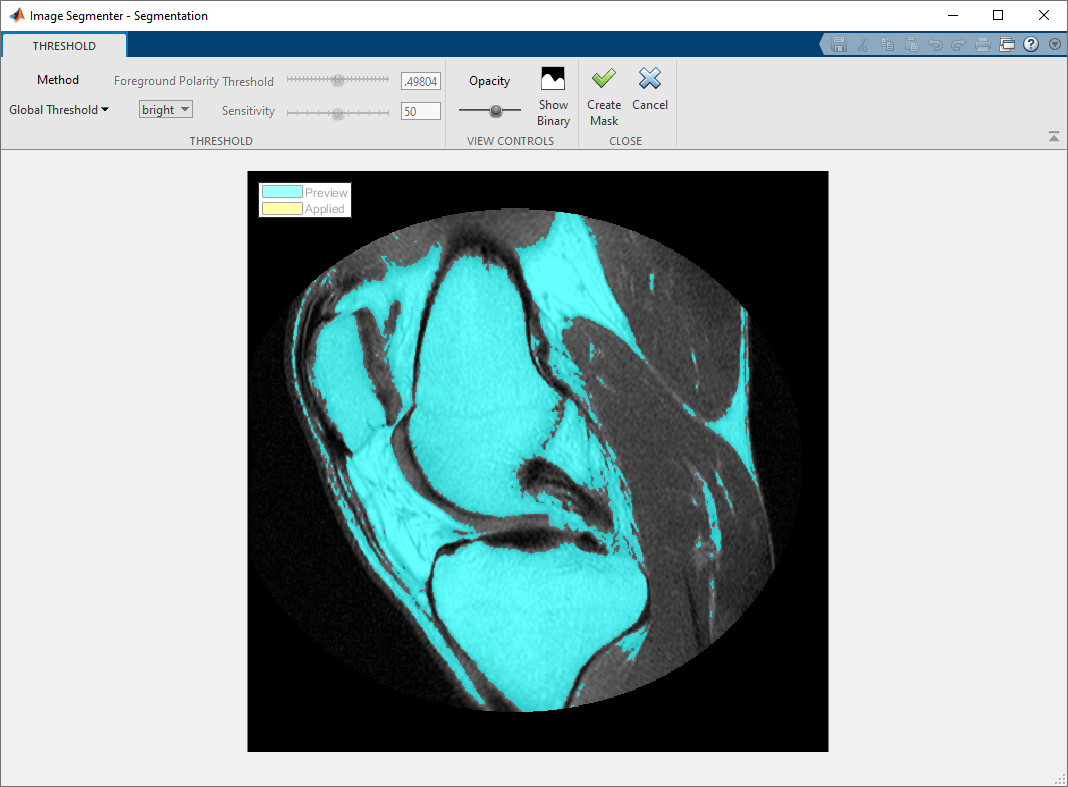

Нажмите Threshold в разделе Create Mask панели инструментов приложения Image Segmenter. Отображения приложения пороговое изображение во вкладке Threshold. По умолчанию приложение использует глобальную пороговую обработку.

Можно также выбрать Manual или Adaptive thresholding. Каждая опция пороговой обработки поддерживает средства управления, которые можно использовать, чтобы подстроить пороговую обработку. Например, с Ручной пороговой обработкой, можно выбрать пороговое значение с помощью ползунка. С Адаптивной пороговой обработкой можно выбрать чувствительность с помощью ползунка. Попробуйте каждую опцию, чтобы видеть, какой метод задания порога выполняет лучшую сегментацию.

Следующий рисунок показывает результаты использования Ручной пороговой обработки.

Изображение колена не имеет четко определенных различий в интенсивности пикселей между передним планом и фоном, и пороговая обработка не походит на лучший выбор сегментировать это изображение.